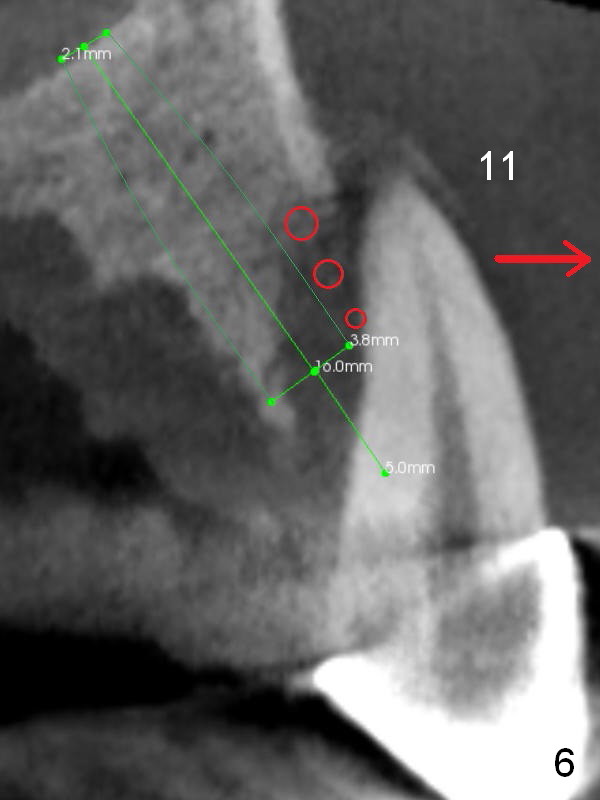

Alginate impression will most likely dislodge #11-15 loose FPD. Start osteotomy at #11 and 15 first (Fig.6, 10) and use the teeth #9 and 10 as trajectory reference. Prepare PRF (Fig.10 white curved line) and Magic Lifter for #15.